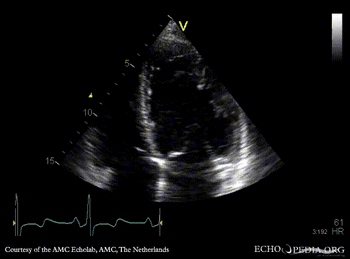

Case 159